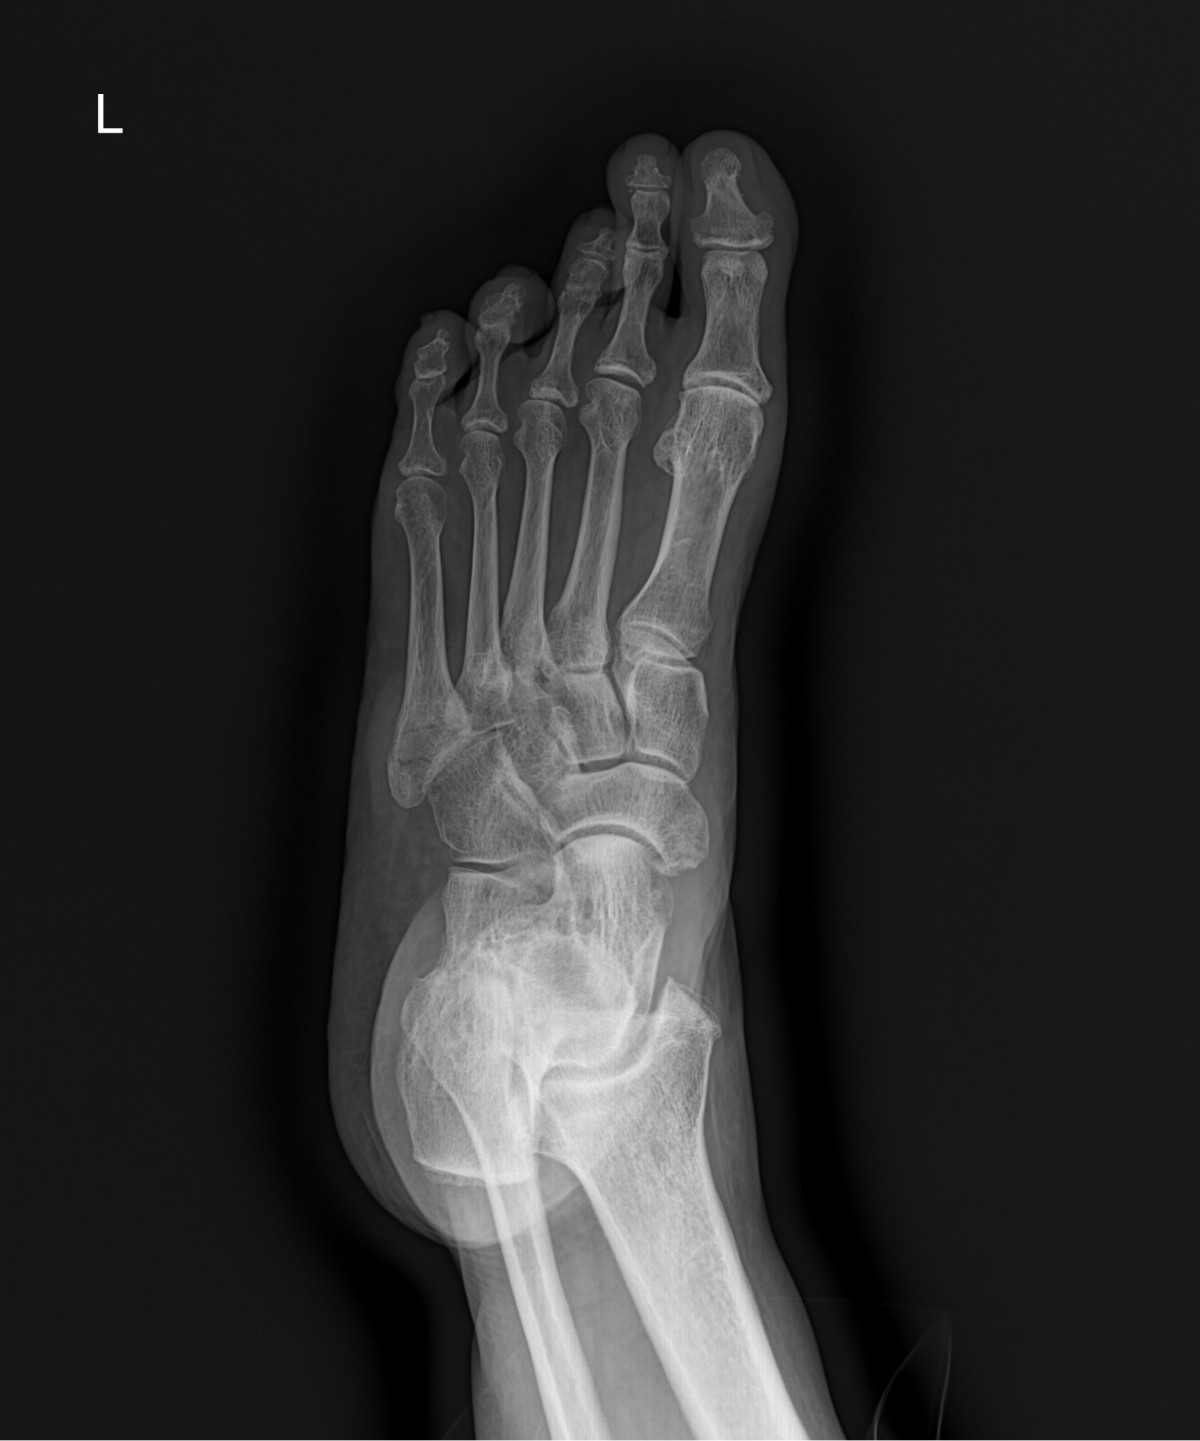

이재상원장님 발등 골절 수술 손선O 환자

dae765e4d9ac96aee867c9d6292d8784_1758003017_8205.jpg